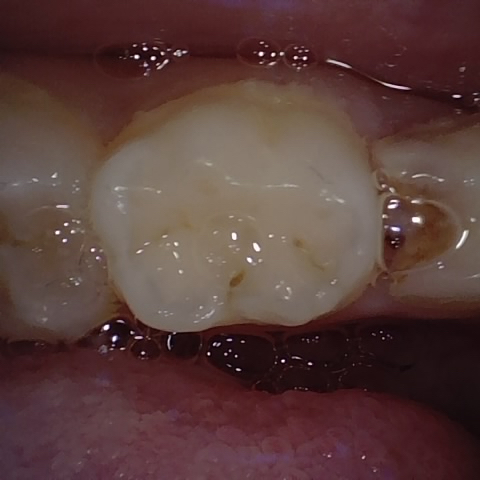

Annotated as "Good"